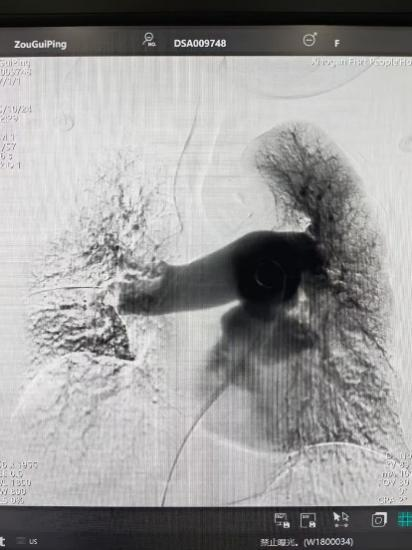

術(shù)后

手術(shù)在局部麻醉下進(jìn)行,團(tuán)隊(duì)通過股靜脈穿刺,將專用抽栓導(dǎo)管精準(zhǔn)送達(dá)肺動(dòng)脈栓塞部位,利用負(fù)壓抽吸技術(shù)成功清除大量血栓;隨后,在血栓局部精準(zhǔn)灌注溶栓藥物,進(jìn)一步溶解殘余血栓,恢復(fù)肺部血流灌注;同時(shí),為防止下肢深靜脈血栓再次脫落引發(fā)肺栓塞,團(tuán)隊(duì)為患者置入下腔靜脈濾器,整個(gè)手術(shù)歷時(shí)約1小時(shí)。術(shù)后,鄒婆婆呼吸困難癥狀即刻得到緩解,血氧飽和度顯著提升,右心負(fù)荷明顯減輕,目前身體狀況正在逐步恢復(fù)中。